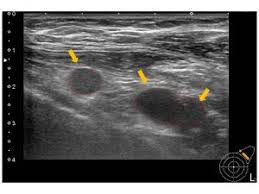

(3) 진단 방법

의료기관에서는 증상에 따라 초음파 검사로 멍울의 형태를 파악하고, 혈액검사로 감염 여부를 확인합니다. 필요시 조직검사를 통해 양성인지 악성인지 판단하게 됩니다.